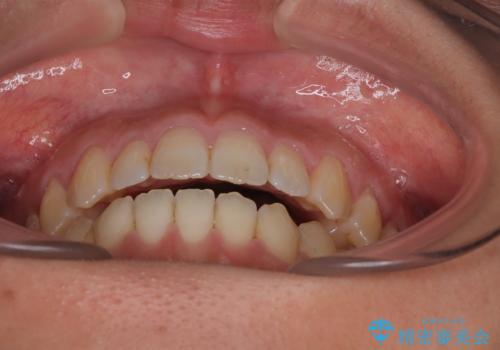

【モニター】食事が取りづらい 極端な開咬をインビザラインで解決

- 極端な開咬を気にして来院された患者様です。

開咬の方の特徴として、幼少期の指しゃぶりの癖や、強い舌の突出癖が挙げられます。

こちらの患者様も強い舌の突出癖が認められたため、矯正治療を行うにあたり、舌のトレーニングをしっかりと行っていただくように指示をいたしました。

開咬はインビザラインが得意とする歯列不正であるため、舌のトレーニングを行いながら、インビザラインにて矯正治療を行うこととしました。

担当医としては、もっと上下の前歯を接触させるところまで治療を進めたいという思いがありますが、今まで咀嚼できなかったものが食べられるようになったということで、この状態で治療終了となりました。